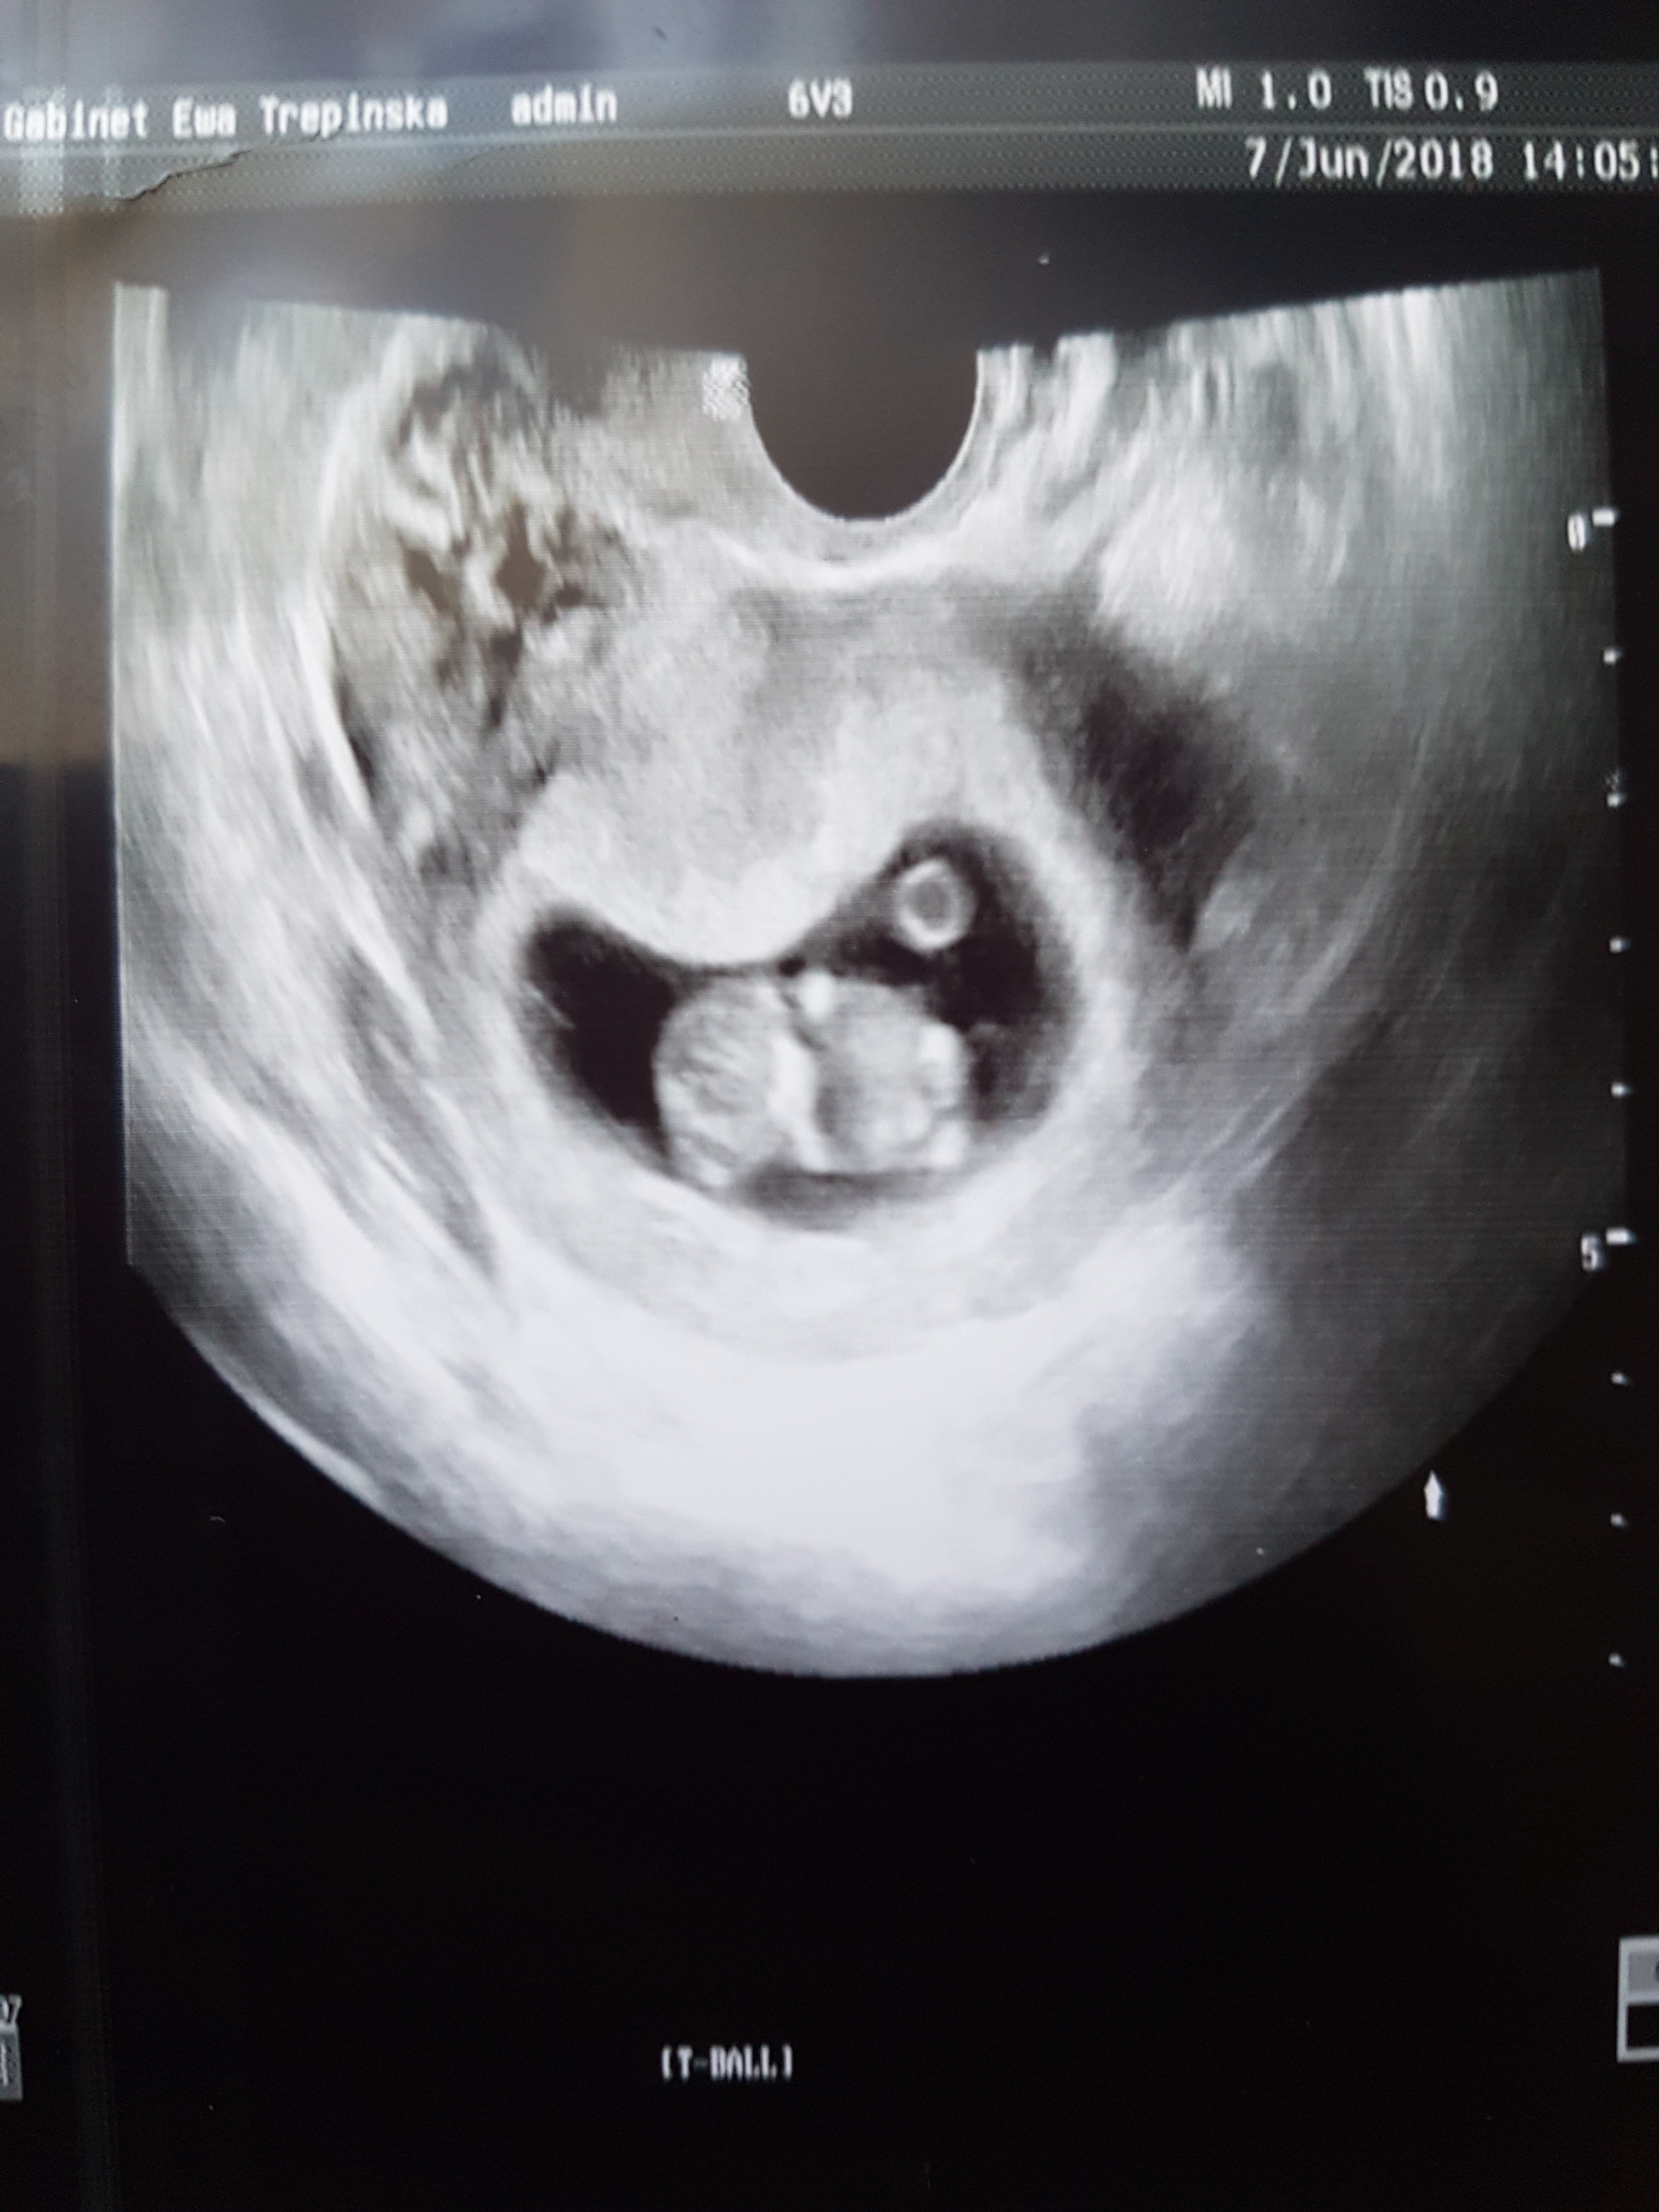

Wow ale super. [emoji8][emoji8][emoji8] Ktory to tydzien?Hallo, Hallo! Mamy się świetnie! Nawet trochę się poruszałem(am) i pomachałem(am) rączkami i nóżkamiZobacz załącznik 864913

Ojej jaka ładna dzidzia[emoji16][emoji250]Hallo, Hallo! Mamy się świetnie! Nawet trochę się poruszałem(am) i pomachałem(am) rączkami i nóżkamiZobacz załącznik 864913

9+3tc.Wow ale super. [emoji8][emoji8][emoji8] Ktory to tydzien?